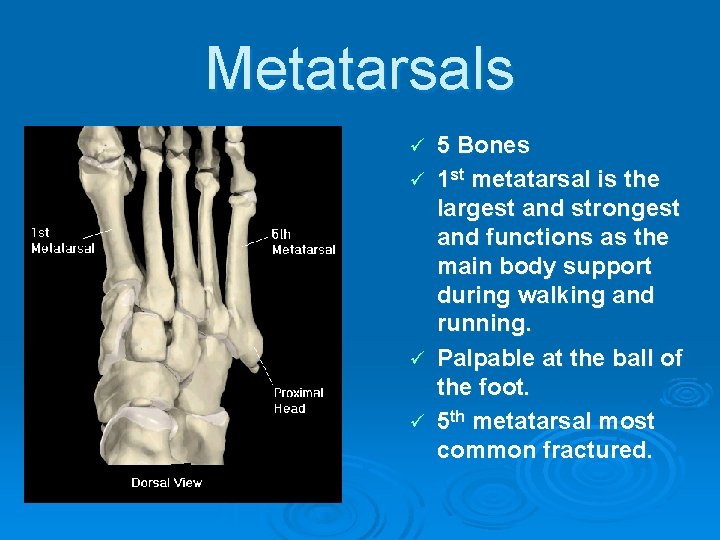

Metatarsals ü ü 5 Bones 1 st metatarsal is the largest and strongest and functions as the main body support during walking and running. Palpable at the ball of the foot. 5 th metatarsal most common fractured.